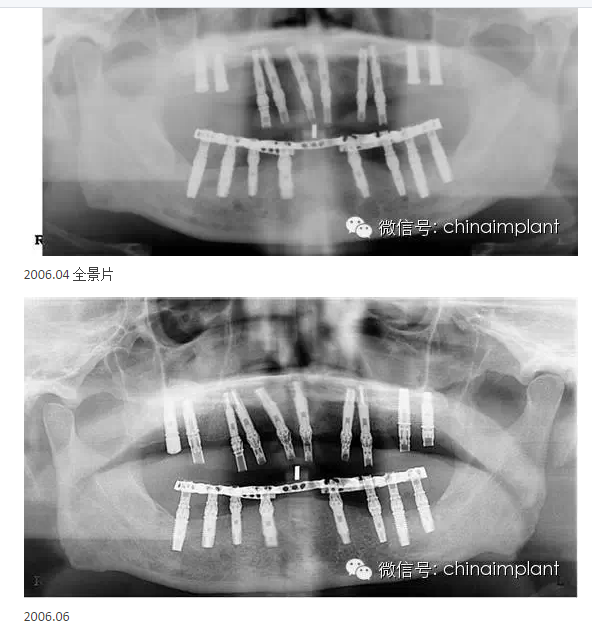

之前針對(duì)全口無(wú)牙進(jìn)行種植修復(fù)的案例中,因?yàn)轭M骨的原因,后期使用橋冠修復(fù)時(shí),一般是3部分(兩側(cè),磨牙,前牙),最近的案例中修復(fù)是一般都是做一體式的橋冠,現(xiàn)在從臨床的修復(fù)案例來(lái)看,沒有什么問(wèn)題。

此案例為術(shù)后兩周戴臨時(shí)牙。過(guò)去因?yàn)閾?dān)心感染的問(wèn)題,一個(gè)月以內(nèi)帶臨時(shí)牙也叫做即刻負(fù)重或者早期負(fù)重。(現(xiàn)在當(dāng)天戴臨時(shí)牙(即刻復(fù)重)的情況也非常常見).

本案例已經(jīng)將近10年了(2005年12月),但是修復(fù)效果個(gè)人認(rèn)為很不錯(cuò),所以拿出來(lái)和大家分享。

從修復(fù)全景片上看到牙齒排列非常好